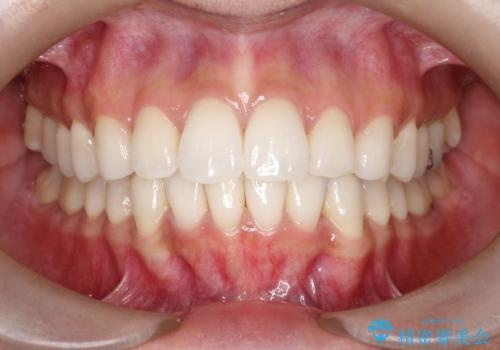

【インビザライン】前歯の凸凹をIPRで改善

- 前歯の凸凹を主訴に来院されました。

前歯を並べるために歯と歯の間にヤスリを入れてわずかに歯を削ることでスペースを確保しています。

歯と歯の間にヤスリを入れてわずかに歯を削ることでスペースを確保する処置をIPRと呼びます。

当院では拡大鏡を用いて丁寧に処置することで歯冠形態を損なわずに行うことができます。